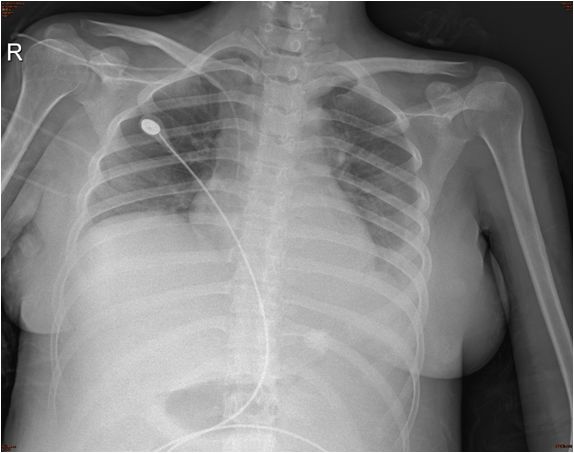

辅助检查-胸片

两肺纹理略增多,左侧胸腔积液